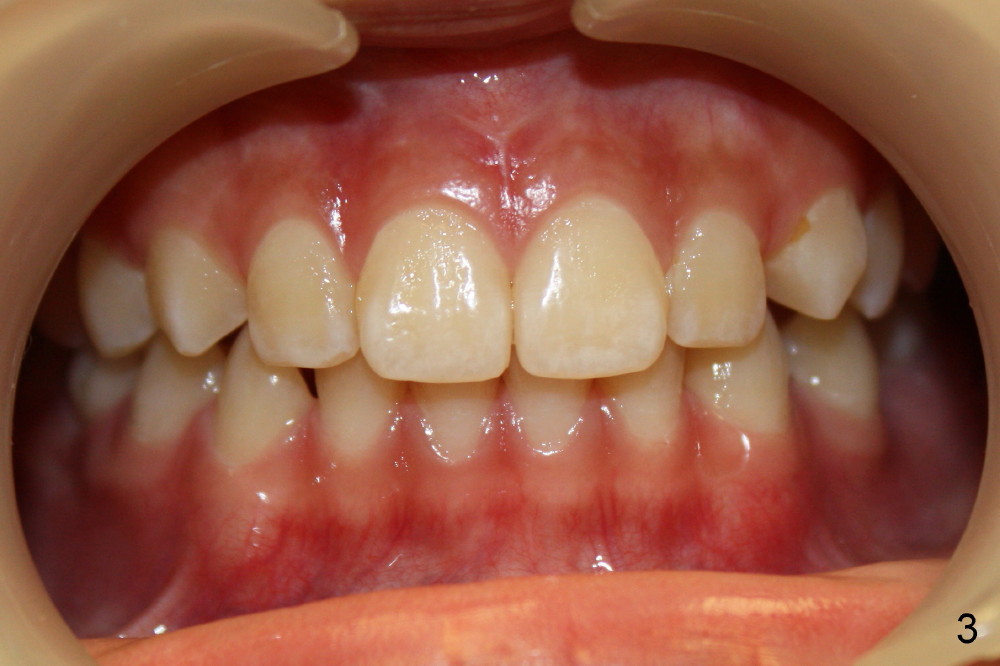

Two lower 2nd bicuspids are congenitally missing in a 11-year-old boy (Fig.1).  The lower left  (LL) E has been extracted due to caries.  There is severe periapical radiolucency associated with the LL6.  Root canal therapy (RCT) is being carried out for this molar with difficulty.  In addition, the boy is a dental phobic, refusing to have the lower right E extracted in spite of DO caries and pain.  In order to reduce the chance of future surgery, including extraction, there are two orthodontic plans to move the lower molars mesially.  Fig.2-4 show that the anterior occlusion and right posterior interdigitation is nearly within normal limit, whereas the left is not.